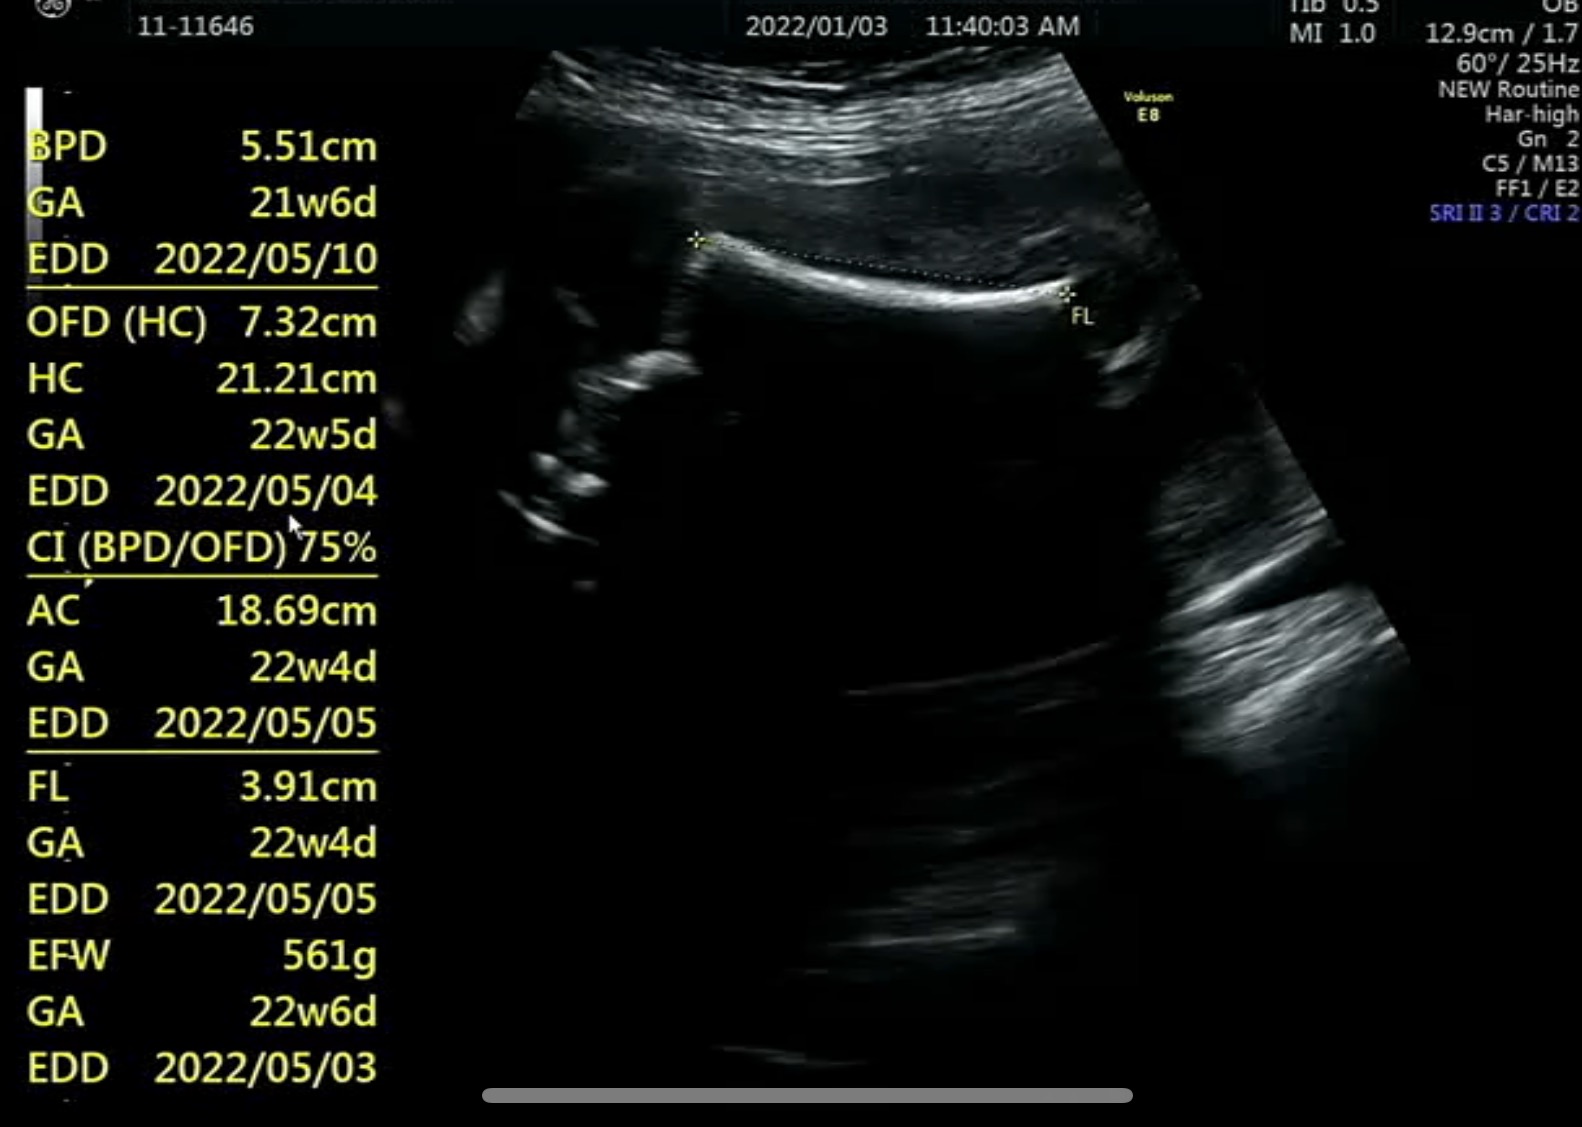

크기가 좀 작긴하지만 문제될 정도는 아니라고 했다.

허벅지 길이가 계속 작게 나오니 다른 부위와 비슷하게 숫자가 나올 따까지 쟀다. ㅋㅋㅋㅋ